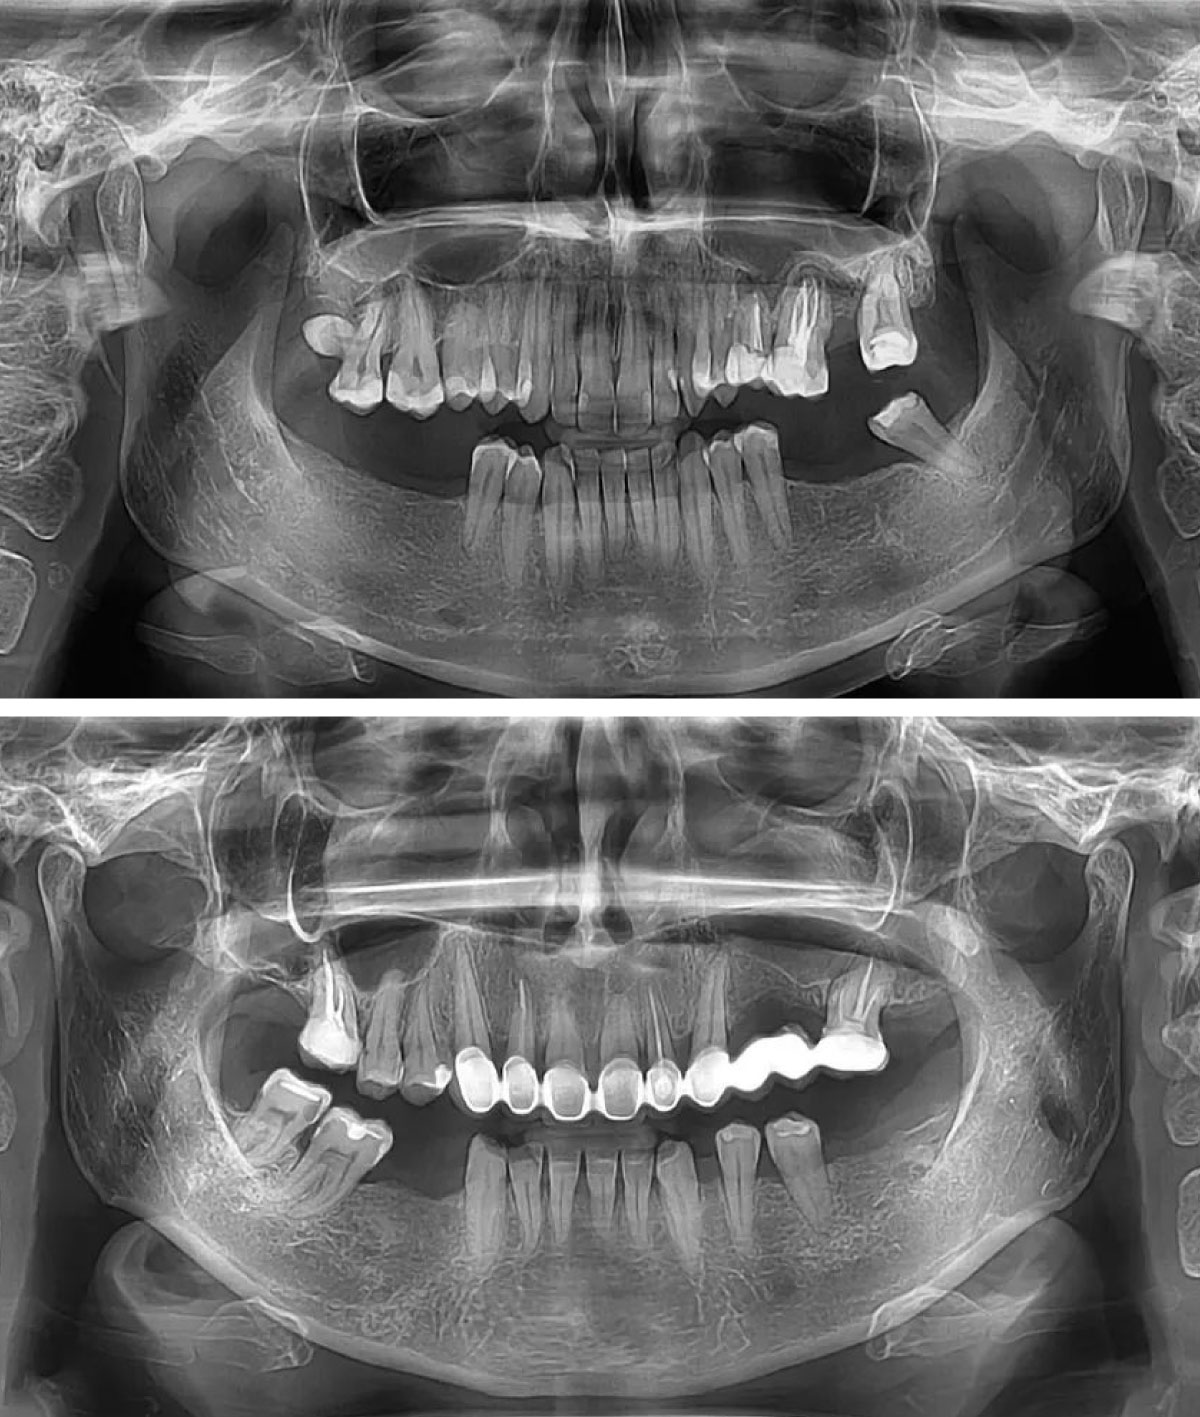

Vrste dentalnih rendgenskih snimaka

Pored ortopan snimka, u stomatologiji se koriste i druge vrste rendgenskih snimanja, u zavisnosti od dijagnostičke potrebe.

Segmentni ortopan

Prikazuje bočne zube gornje i donje vilice na jednom snimku. Najčešće se koristi za otkrivanje karijesa između zuba i procenu nivoa kosti.

Full Mouth Series (FMX)

Predstavlja seriju više pojedinačnih snimaka kojima se detaljno prikazuju svi zubi i okolna tkiva.